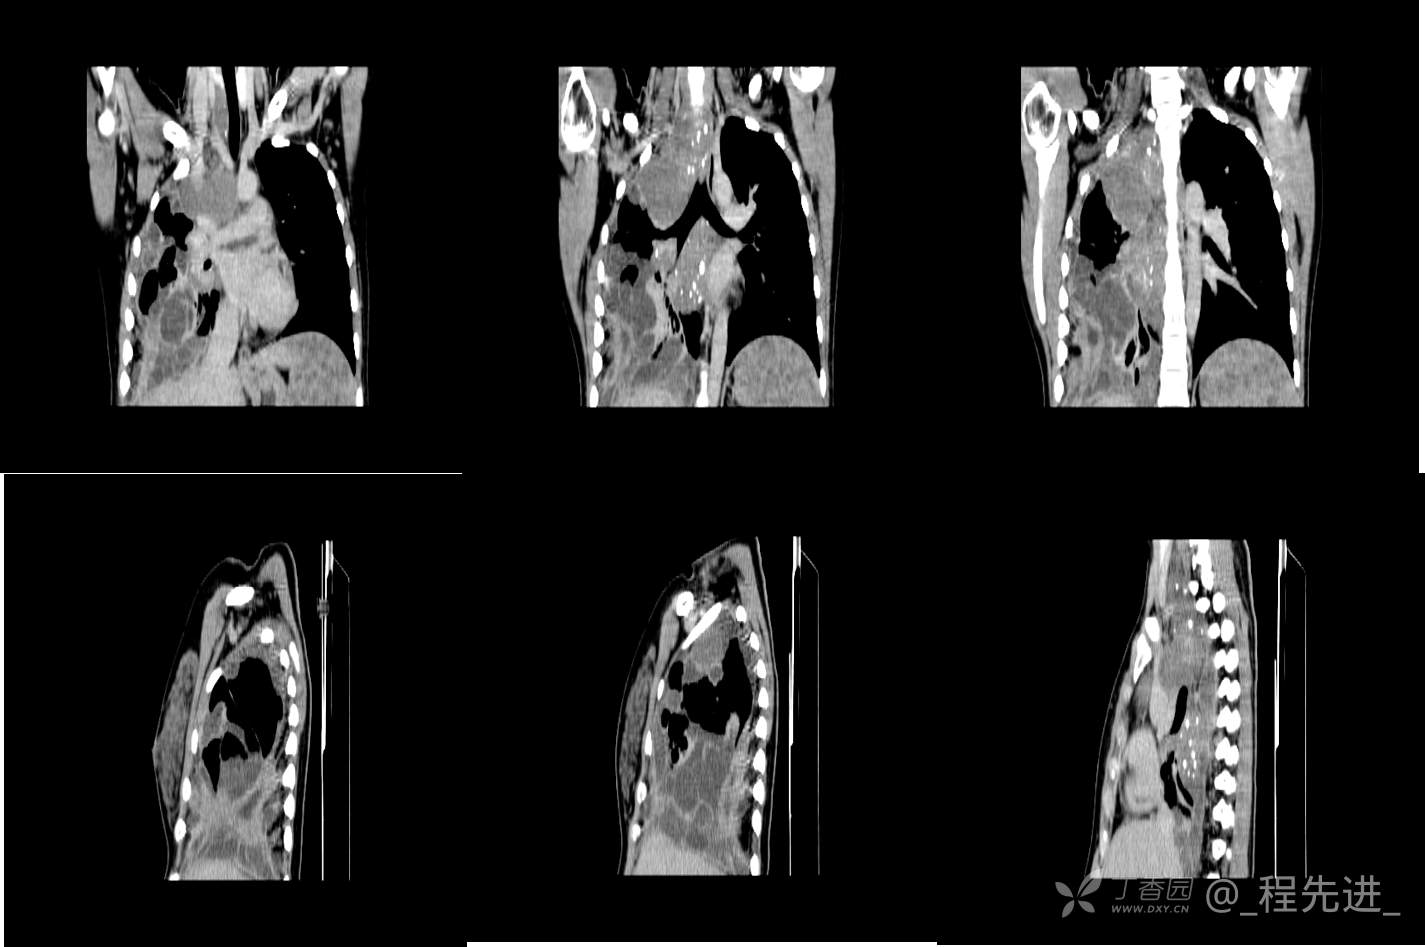

患者性别:女

患者年龄:26岁

简要病史:反复胸闷、气喘、咳嗽半年